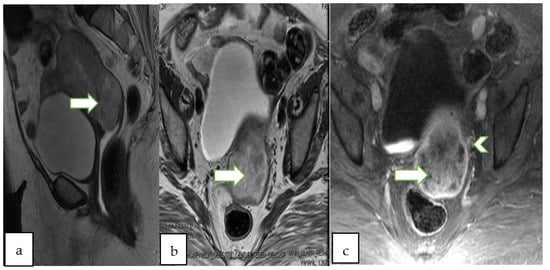

4.2. Magnetic Resonance Imaging (MRI)

- Bourgioti, C.; Chatoupis, K.; Antoniou, A.; Panourgias, E.; Tzavara, C.; Rodolakis, A.; Moulopoulos, L. T2-weighted MRI findings predictive of parametrial involvement in patients with cervical cancer and histologically confirmed full thickness stromal invasion. Hell. J. Radiol. 2018, 3, 23–32. [Google Scholar]

- Otero-García, M.M.; Mesa-Álvarez, A.; Nikolic, O.; Blanco-Lobato, P.; Basta-Nikolic, M.; de Llano-Ortega, R.M.; Paredes-Velázquez, L. Role of MRI in staging and follow-up of endometrial and cervical cancer: Pitfalls and mimickers. Insights Imaging 2019, 10, 19. [Google Scholar] [CrossRef]